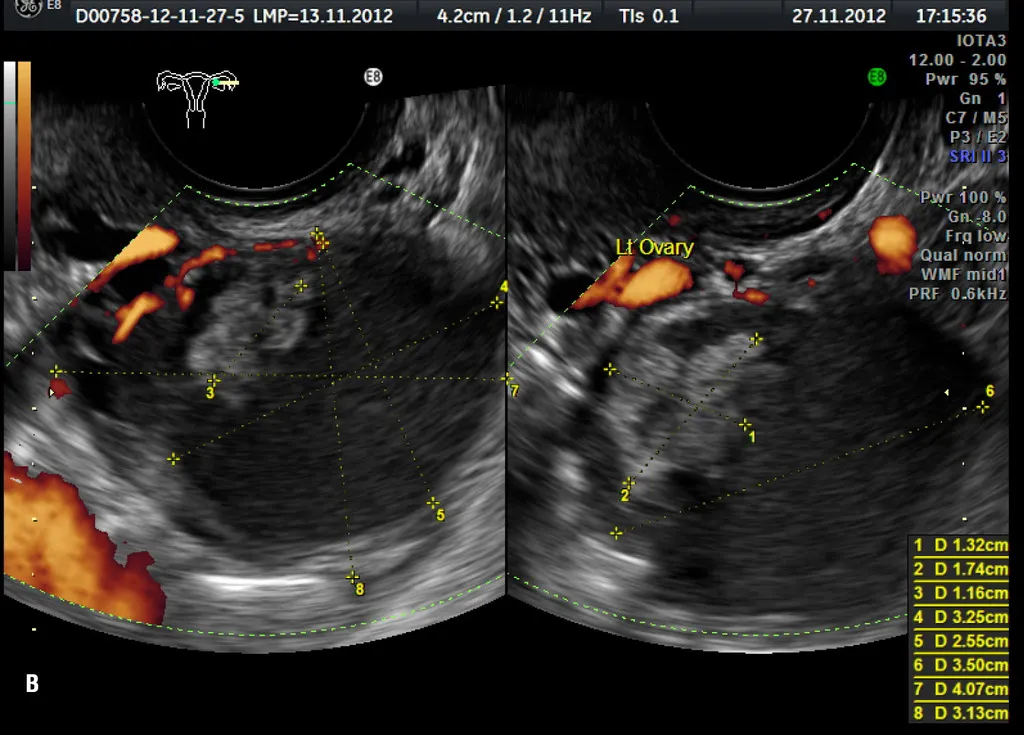

Test ROMA, czyli Risk of Ovarian Malignancy Algorithm, to zaawansowany algorytm diagnostyczny, który odgrywa kluczową rolę w ocenie ryzyka wystąpienia złośliwego, nabłonkowego raka jajnika. Stosuje się go u kobiet, u których podczas badania, na przykład USG, wykryto guz w obrębie miednicy mniejszej. Moim zdaniem, jego znaczenie w kontekście wczesnej diagnostyki jest nie do przecenienia, ponieważ pozwala lekarzom na szybsze i bardziej precyzyjne podjęcie decyzji o dalszym postępowaniu, co jest kluczowe w walce z tym podstępnym nowotworem.

Głównym wskazaniem do wykonania testu ROMA jest wykrycie jakiejkolwiek zmiany guza, torbieli w jajnikach lub w obrębie miednicy mniejszej podczas rutynowego badania, najczęściej USG. Celem tego badania jest przede wszystkim różnicowanie, czy wykryta zmiana ma charakter łagodny, czy też istnieje potencjalne ryzyko, że jest ona złośliwa. To kluczowy moment, w którym test ROMA może znacząco pomóc w podjęciu dalszych decyzji diagnostycznych i terapeutycznych.